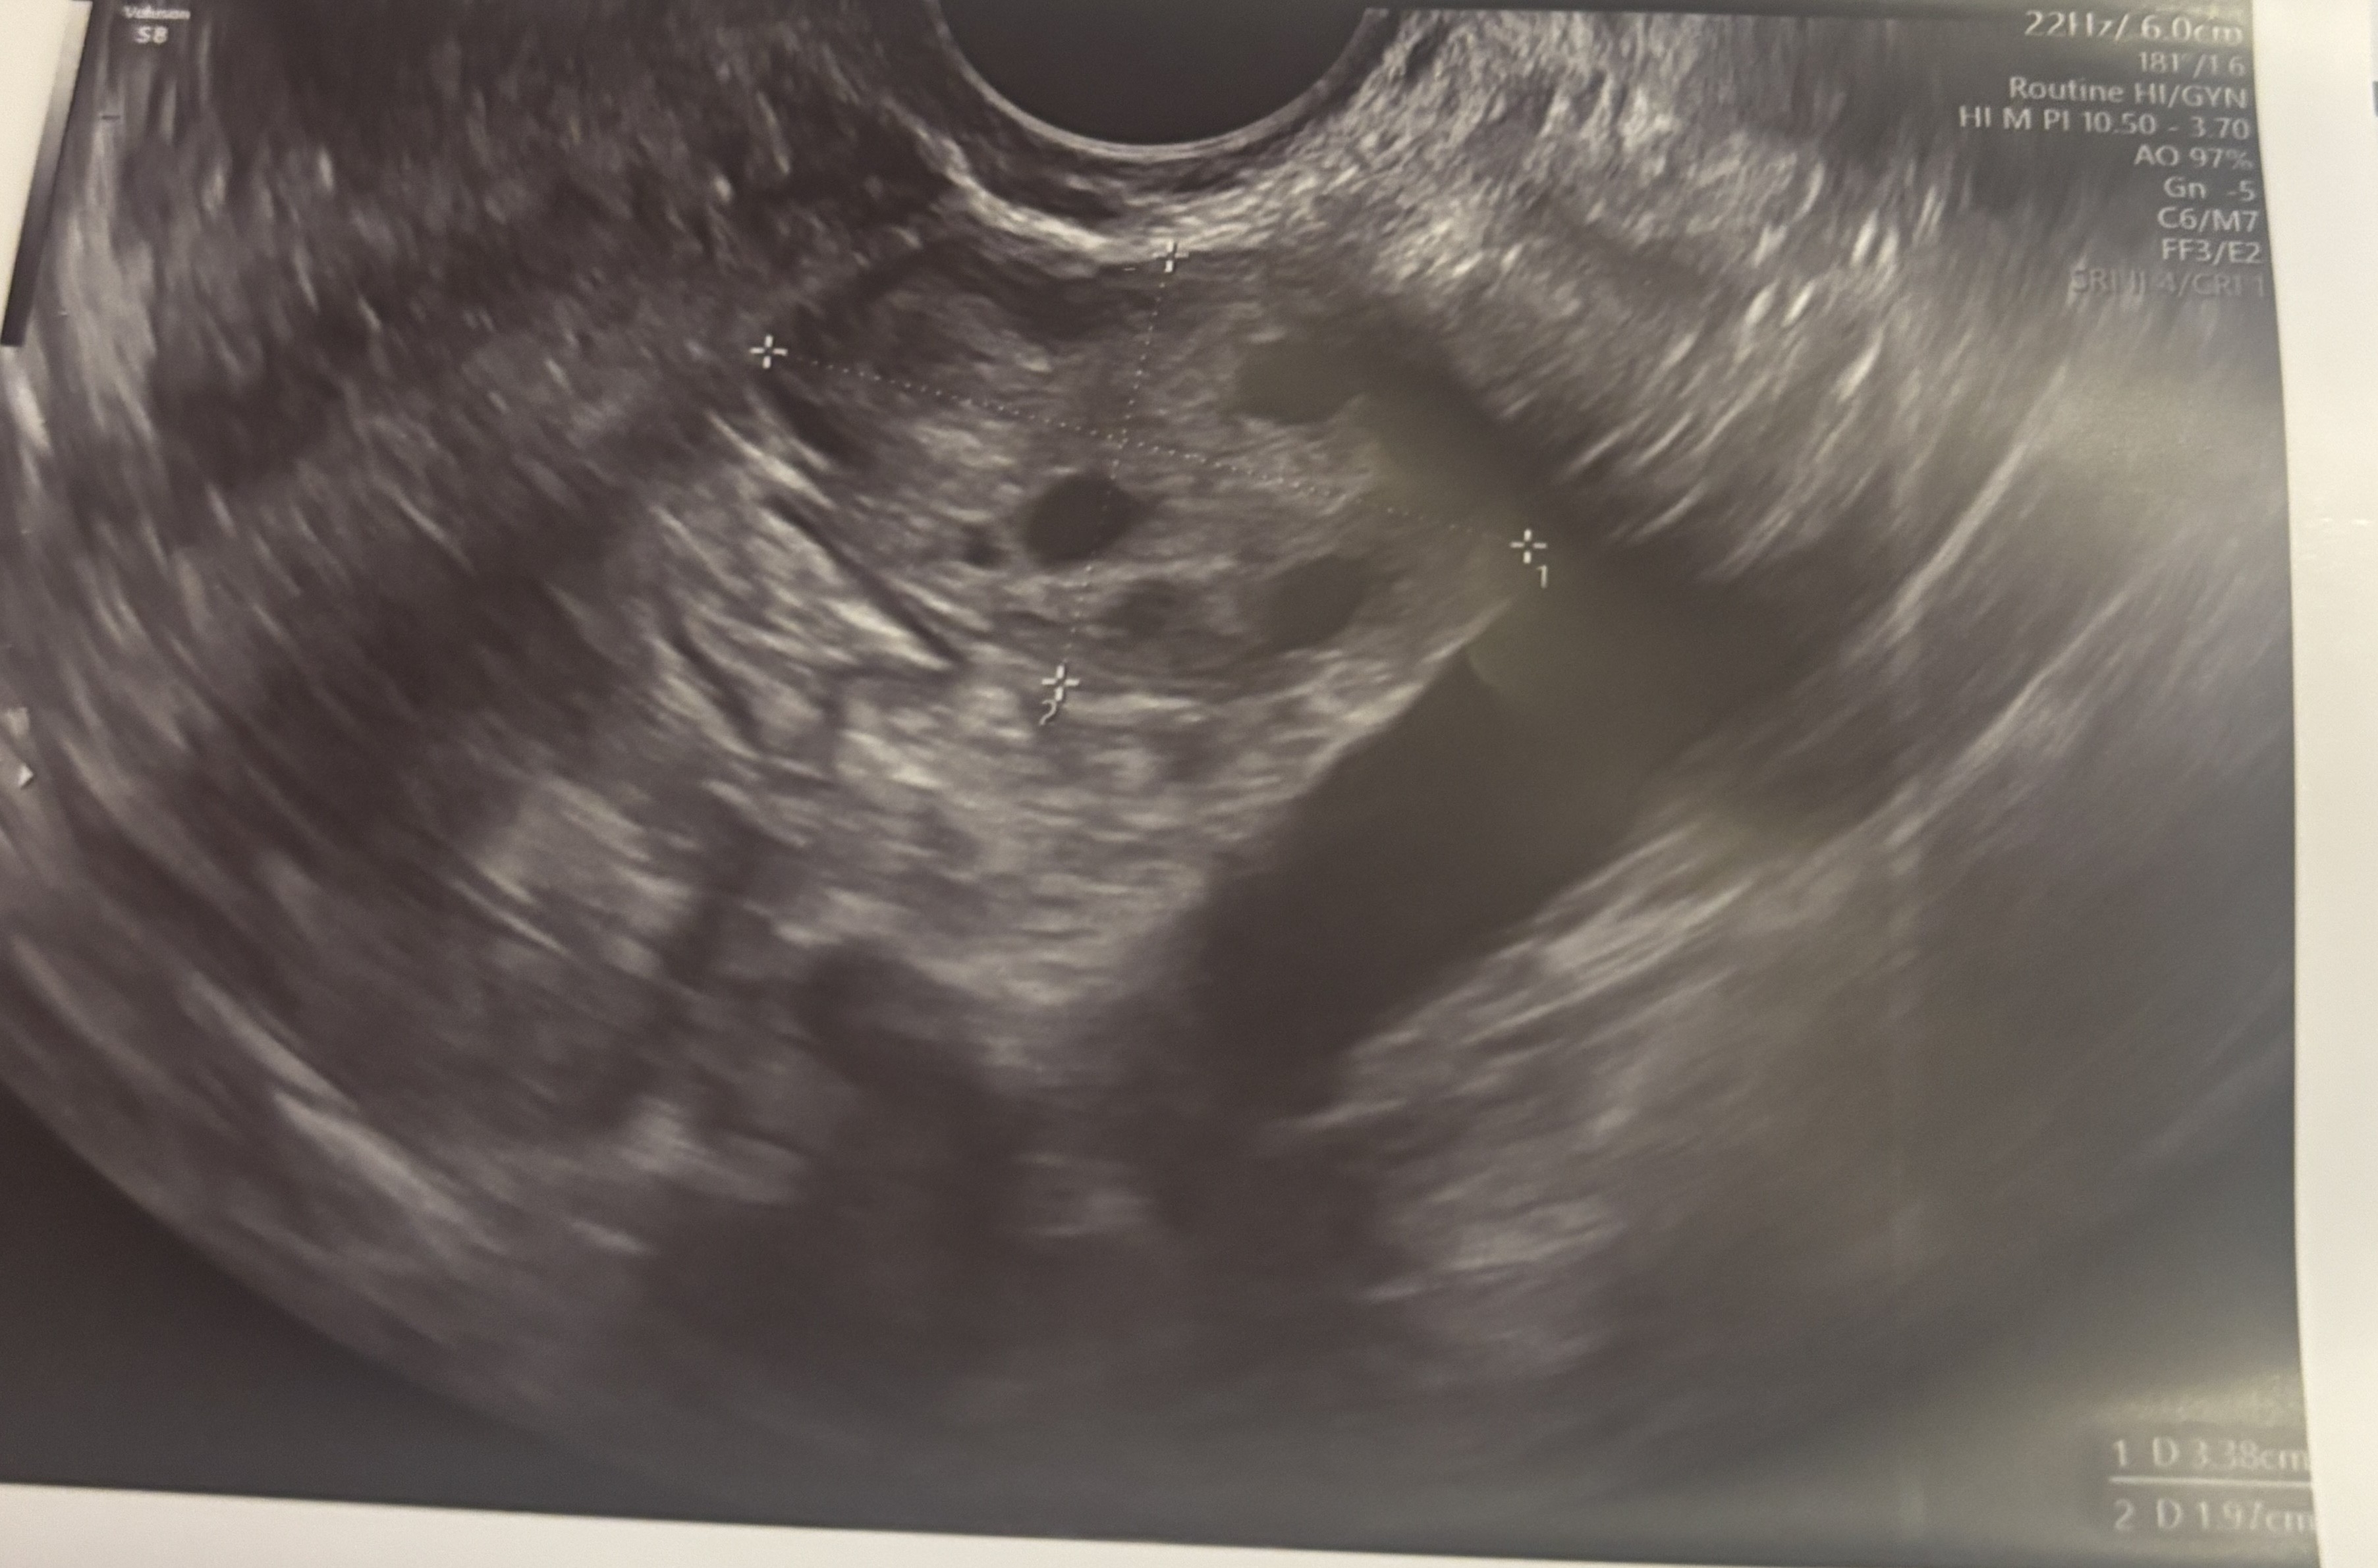

USG- czy widoczny pęcherzyk owulacyjny?

Może zna się któraś z Was, i powie mi czy widzicie na tych zdjęciach USG pęcherzyk owulacyjny?

Na jednym jajniku mam torbiel, ale ginekolog nie kazała się martwić bo jestem po poronieniu.

Endometrium mam 8,3 mm.